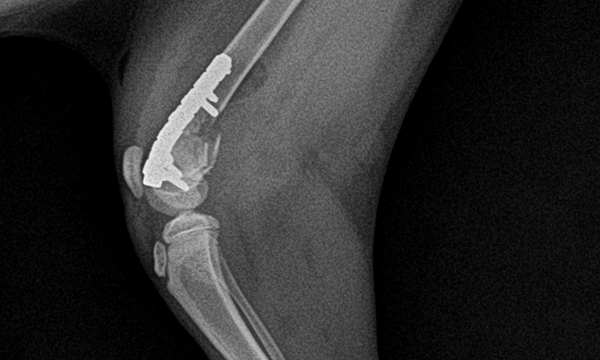

수술케이스 ③ 배*강아지 - 대퇴골 분쇄골절

수술케이스 3 before BEFORE

수술케이스 3 after AFTER